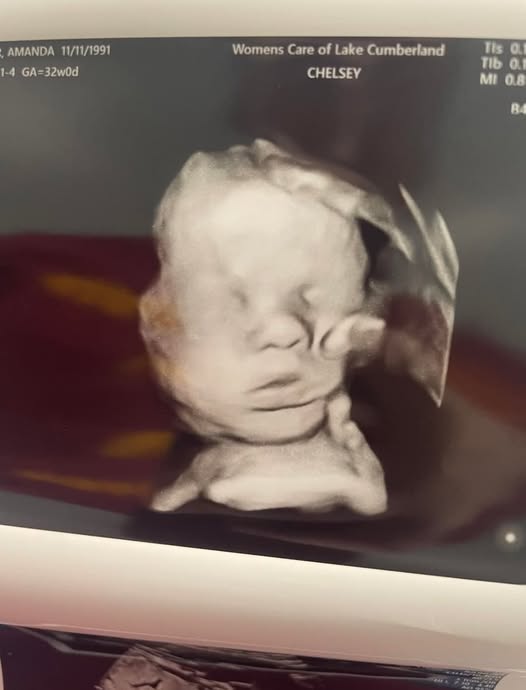

“I had an ultrasound yesterday, my youngest daughter Bailey was the first to notice it and asked me whose hand that was,” she writes in her now viral Facebook post. The post also includes a black and white image of the ultrasound, showing what she believes to be a divine presence of a giant hand cradling her son’s head. She adds: “In one of his pictures it has the appearance of a hand holding his head.”

She adds that the sight of the hand allegedly supporting Kyler’s head brought her to “tears” over “all [God] has and continues to do for me. And I couldn’t ever fathom a thought of living without [God] in my life!”